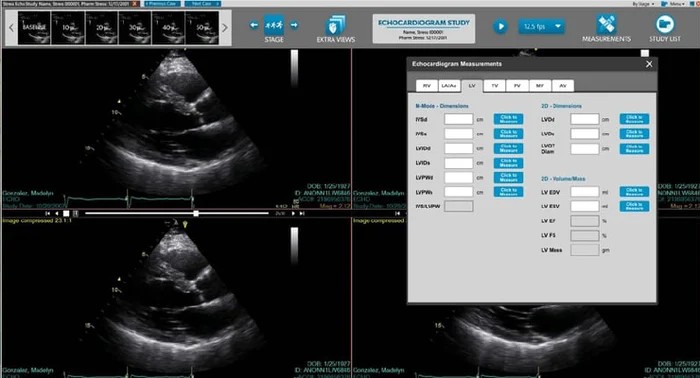

Salt Lake City, Sept. 30, 2025 (GLOBE NEWSWIRE) -- Novarad® is proud to announce the successful installation of its NovaCardio® CVIS as the chosen solution integrated with EncaptureMD™ Structured Reporting at Capitol Medical Center, a leading hospital in Quezon City, Philippines. This milestone installation brings Capitol Medical to a fully integrated, modernized cardiology workflow that enhances efficiency, accuracy, and patient care.

- NovaCardio cardiologist viewer for advanced imaging review

- On-site Non-Invasive Structured Reporting

- Structured reporting modules for Echo and Vascular studies